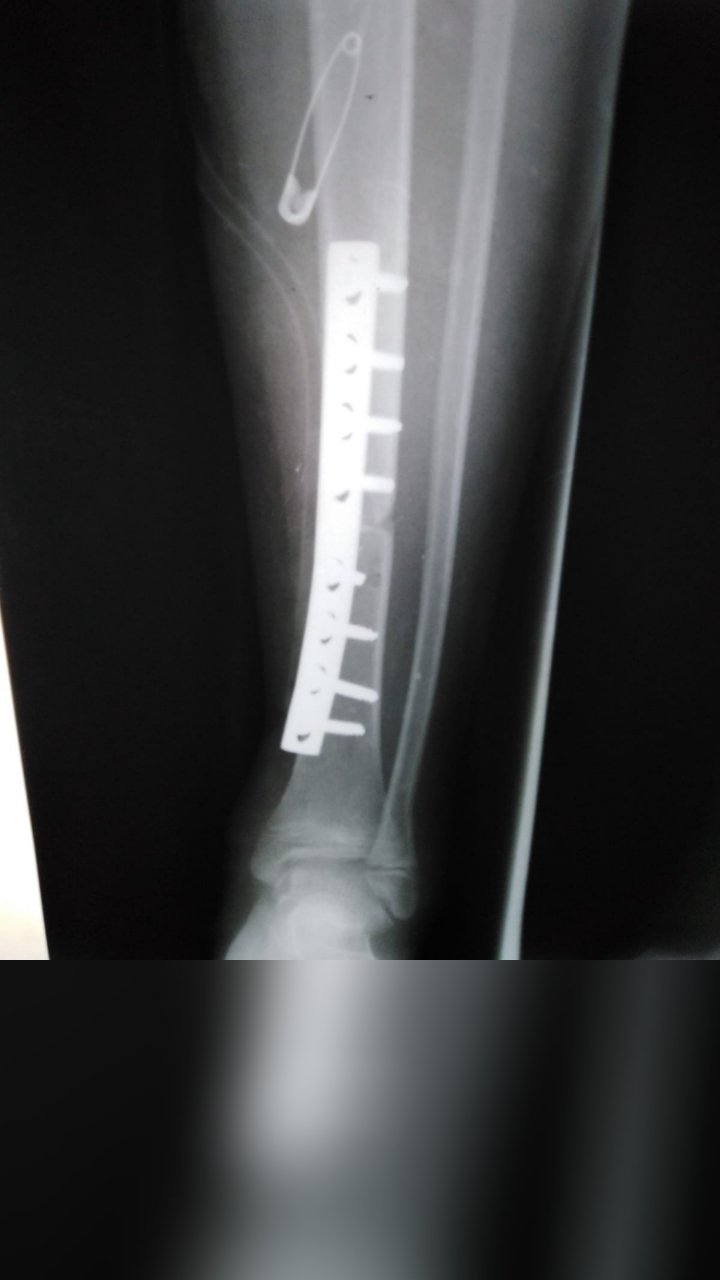

ANKLE FRACTURE SURGERY

TIBIA FRACTURE SURGERY